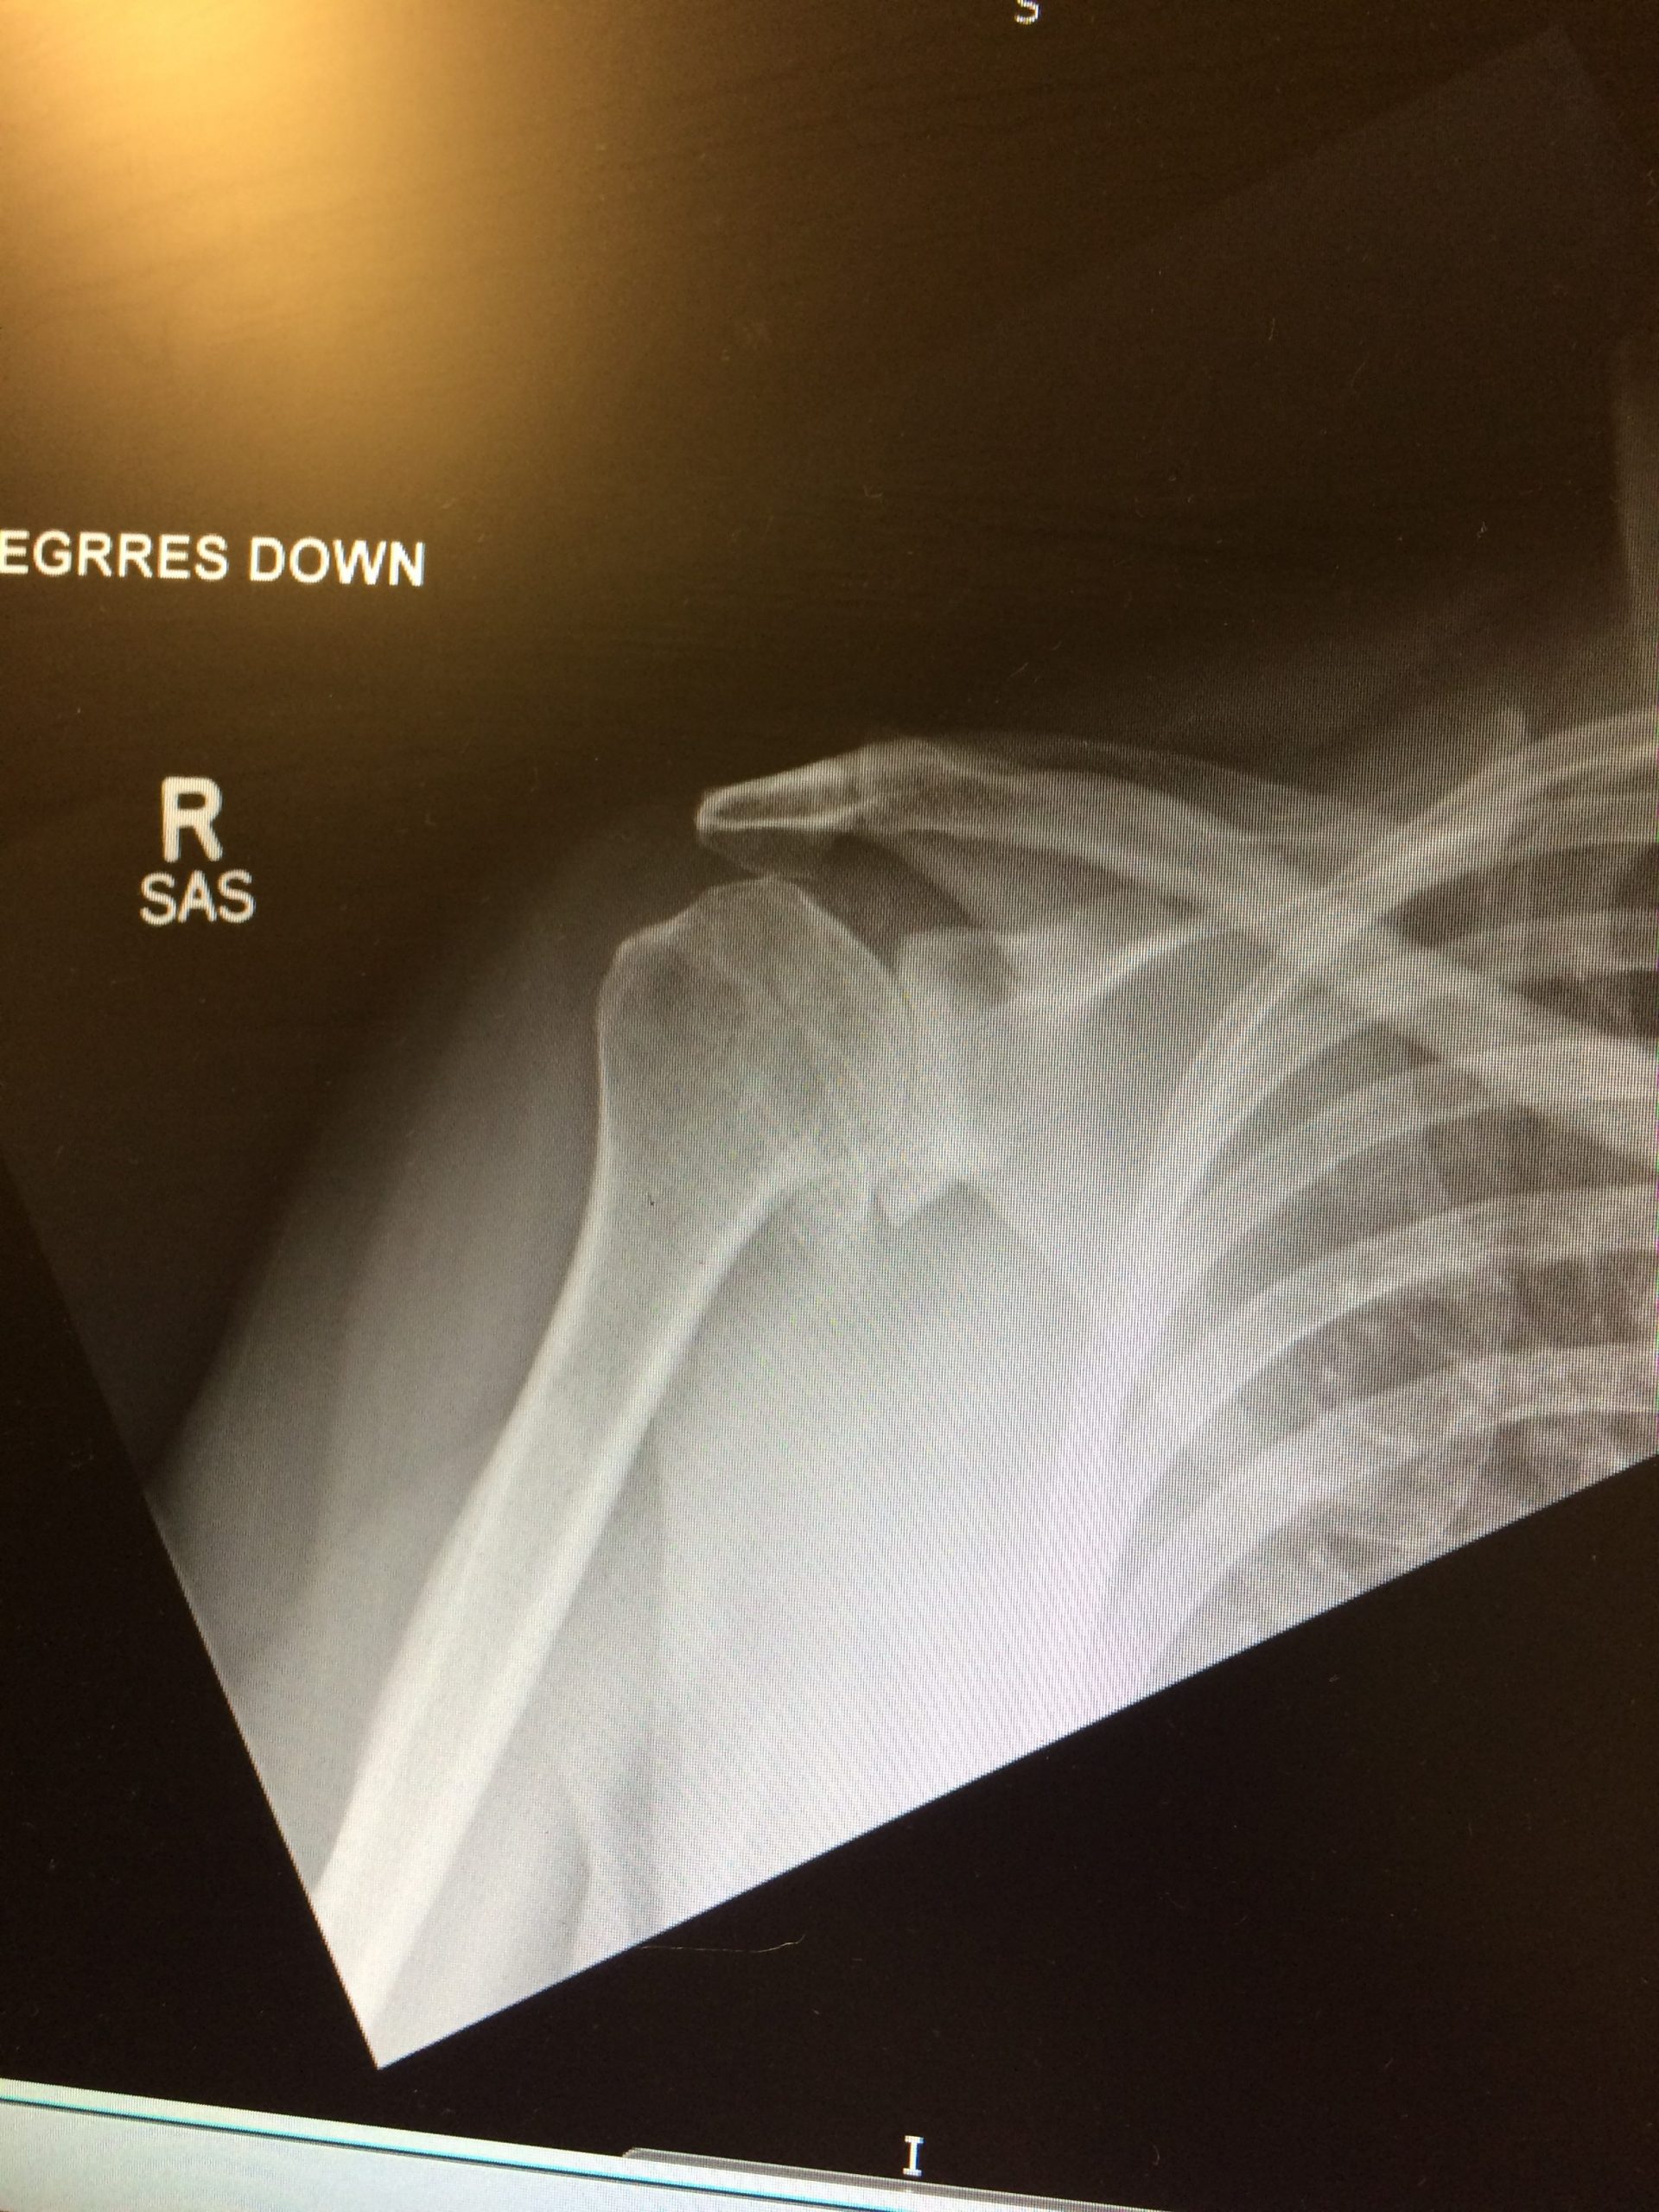

Impingement Syndrome is a condition which occurs when the tendons of the shoulder muscles called Rotator Cuff become irritated and inflamed as they pass through (the subacromial space) the passage beneath the arch of shoulder blade called Acromion. This can result in pain, weakness and loss of movement at the shoulder

The range of motion at the shoulder may be limited by pain. A painful arc of movement may be present during forward elevation of the arm from 60° to 120°. Passive movement at the shoulder will appear painful when a downwards force is applied at the acromion but the pain will ease once the downwards force is removed.